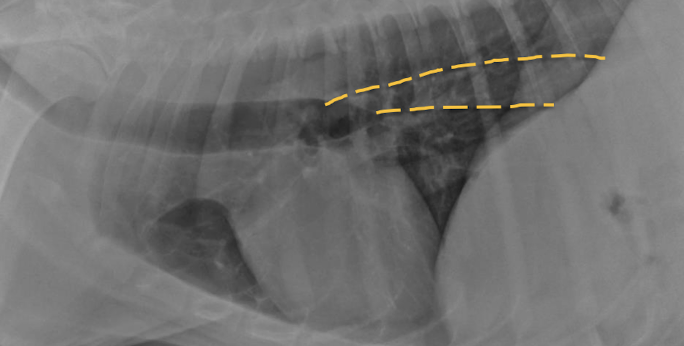

Esophageal dilation